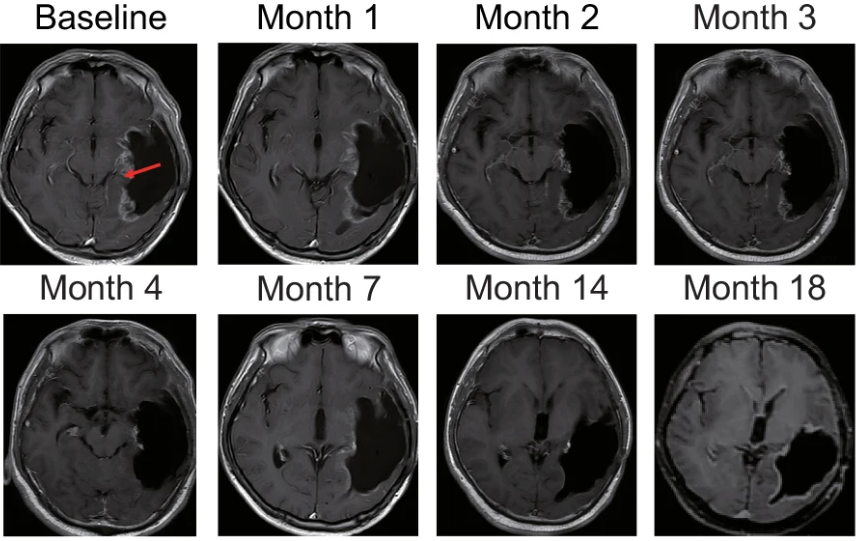

8例患者入组接受Ad-TD-nsIL12治疗,结果显示:中位总生存期为18.9 个月,患者6 肿瘤完全消失,达到完全缓解(CR),患者4达到部分缓解(PR),4例患者病情稳定(SD)。患者6 最初表现为持续 8 个月的头晕、左视力下降和失语异常。左颞叶有 T1 高信号肿块,放疗和同步替莫唑胺治疗后,发现切除腔边缘出现新进展,复发性肿块位于切除腔的内侧壁。治疗后第7 个月肿瘤增强图像消失,18 个月时未观察到明显的肿瘤增强。